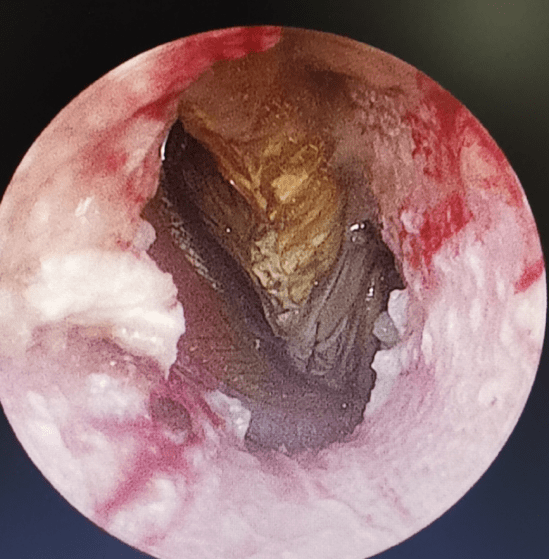

考虑到直接钳取 , 会激惹蟑螂钻得更深 , 又考虑到蟑螂有翅膀和触须 , 用钳子容易夹碎 , 导致不能完整取出 , 给患者带来更大痛苦和损伤 。 庞锋通过在耳道内滴入油剂如石蜡油 , 可以使蟑螂窒息 , 同时油性物质的润滑作用又减少了蟑螂爬动对外耳道皮肤和鼓膜的损伤 , 使之更容易取出 。 随后将窒息的蟑螂取出 , 对患者外耳道进行清理 。

取出蟑螂后的外耳道伴有皮肤和鼓膜损伤、出血